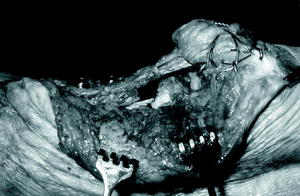

Mujer de 18 años que tras un accidente de tráfico presentó una fractura abierta grado III-B de Gustilo16 de su rodilla izquierda, con importante perdida cutánea y ósea por abrasión, que afectaba 2 tercios del cóndilo femoral y meseta tibial externa y la mitad inferior de rótula, así como perdida completa del tendón rotuliano y déficit motor y sensitivo del nervio ciático poplíteo externo.

A las 48 horas se realizó un segundo desbridamiento y cobertura del defecto cutáneo con un colgajo libre muscular de dorsal ancho, con pedículo vascular toracodorsal y anastomosis microquirúrgica a vasos poplíteos, e injerto mallado de piel tomado del muslo izquierdo. Se colocó una tracción transrrotuliana para evitar la retracción del aparato extensor que se mantuvo durante 2 semanas. A los 10 días se realizó un nuevo desbridamiento, ante la aparición de una infección superficial de las heridas por Stafilococus aureus, así como tratamiento antibiótico especifico que se mantuvo durante 5 semanas. Finalmente, la infección se controló y se logró la epitelización de las heridas, en algunas zonas por segunda intención.